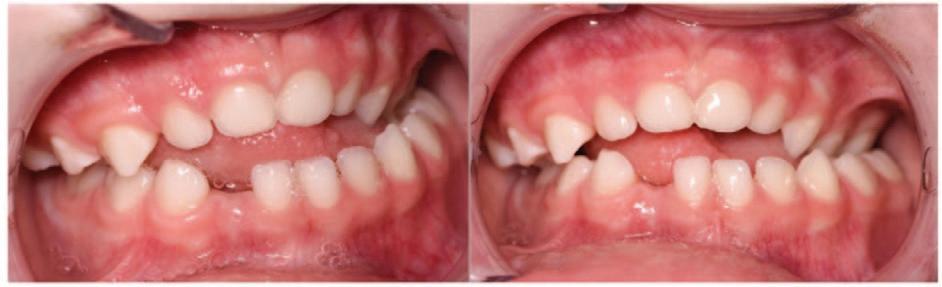

This patient first attended the Oral Surgery Department of Royal School of Dentistry Belfast for removal of a compound odontome in the right mandibular premolar region. This was an incidental finding discovered during assessment for orthodontic treatment (Figure 1). There was no evidence at that time of any other supernumerary teeth elsewhere in the jaws. This compound odontome tooth was surgically removed at that time following the informed consent process. The patient subsequently completed orthodontic treatment. Eight years later, at the age of 21, the patient was referred to the Oral Surgery Department for a second time due to the incidental finding of another supernumerary tooth on the contralateral side (Figure 2). The patient reported no relevant medical or genetic conditions. There was no reported family history

of supernumerary teeth. Clinical examination at age 21 years revealed a wellaligned dentition with a maxillary bonded retainer in place (Figure 2). No symptoms were reported related to the supernumerary teeth. None of the teeth were tender to percussion and all adjacent teeth exhibited a positive response to ethyl chloride. There was a palpable lingual bulge in the alveolar region of the lower left second premolar and first permanent molar. The panoramic radiograph indicated the presence of a radiopaque lesion and a radiolucent lesion in the left mandibular premolar region (Figure 3). A conebeam computed tomography scan was recorded to further characterise the lesion and surrounding area to aid surgical planning (Figure 4).

A maxillofacial radiology report confirmed the presence of fused supernumerary teeth with abnormal crown forms, with an inferiorly located mixed density lesion. The circular mixed density lesion had a radiodense periphery and a radiolucent core superimposed by the inferior alveolar canal. The follicle of the fused supernumeraries and that of the mixed density lesion were confluent. The mixed density lesion was consistent with an invaginated (dilated) odontome. Minor root resorption was reported into the outer dentine of the lower left premolar and lower left first molar.